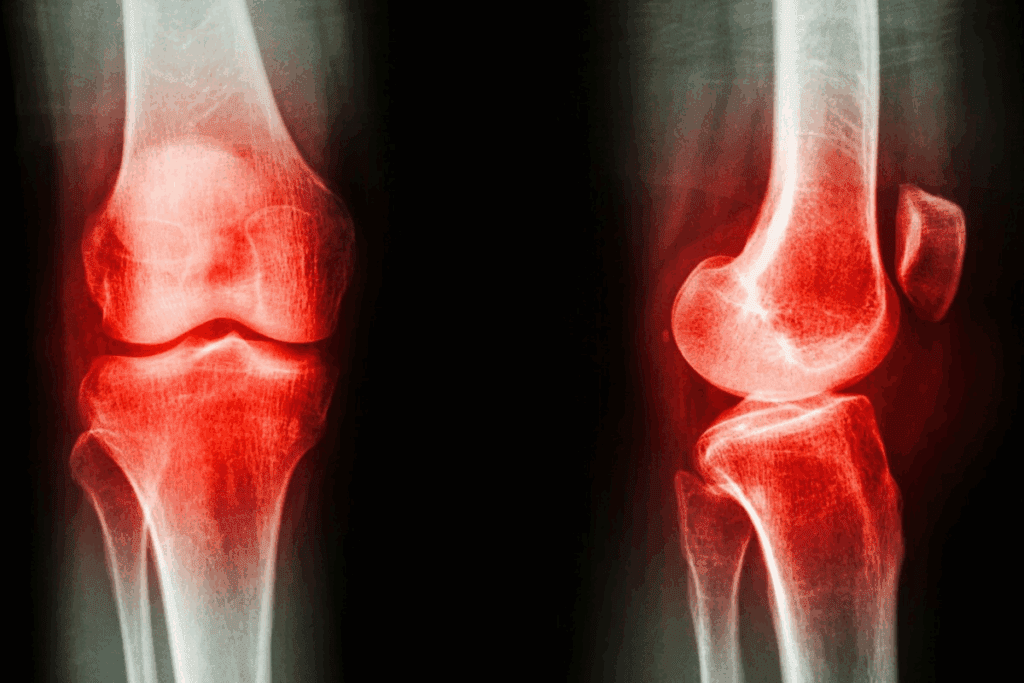

The knee joint is complex and heavily used, making it prone to pain and injuries. Knowing about knee pain is key to managing and treating it effectively.

Anatomy of the Knee Joint

The knee joint connects the femur (thigh bone) to the tibia (shin bone). It’s stabilized by ligaments and supported by muscles and tendons. This joint allows for flexion and extension, enabling a wide range of movements.

The key components of the knee joint include:

- Ligaments: Providing stability and support

- Tendons: Connecting muscles to bones

- Meniscus: Cartilage structures that cushion the joint

- Synovial membrane: Producing fluid that lubricates the joint

Imaging tests are vital for diagnosing knee pain. X-rays check bone health and look for fractures or wear and tear. Magnetic Resonance Imaging (MRI) shows soft tissue details, like ligaments and cartilage, helping spot injuries or conditions like tendinitis.